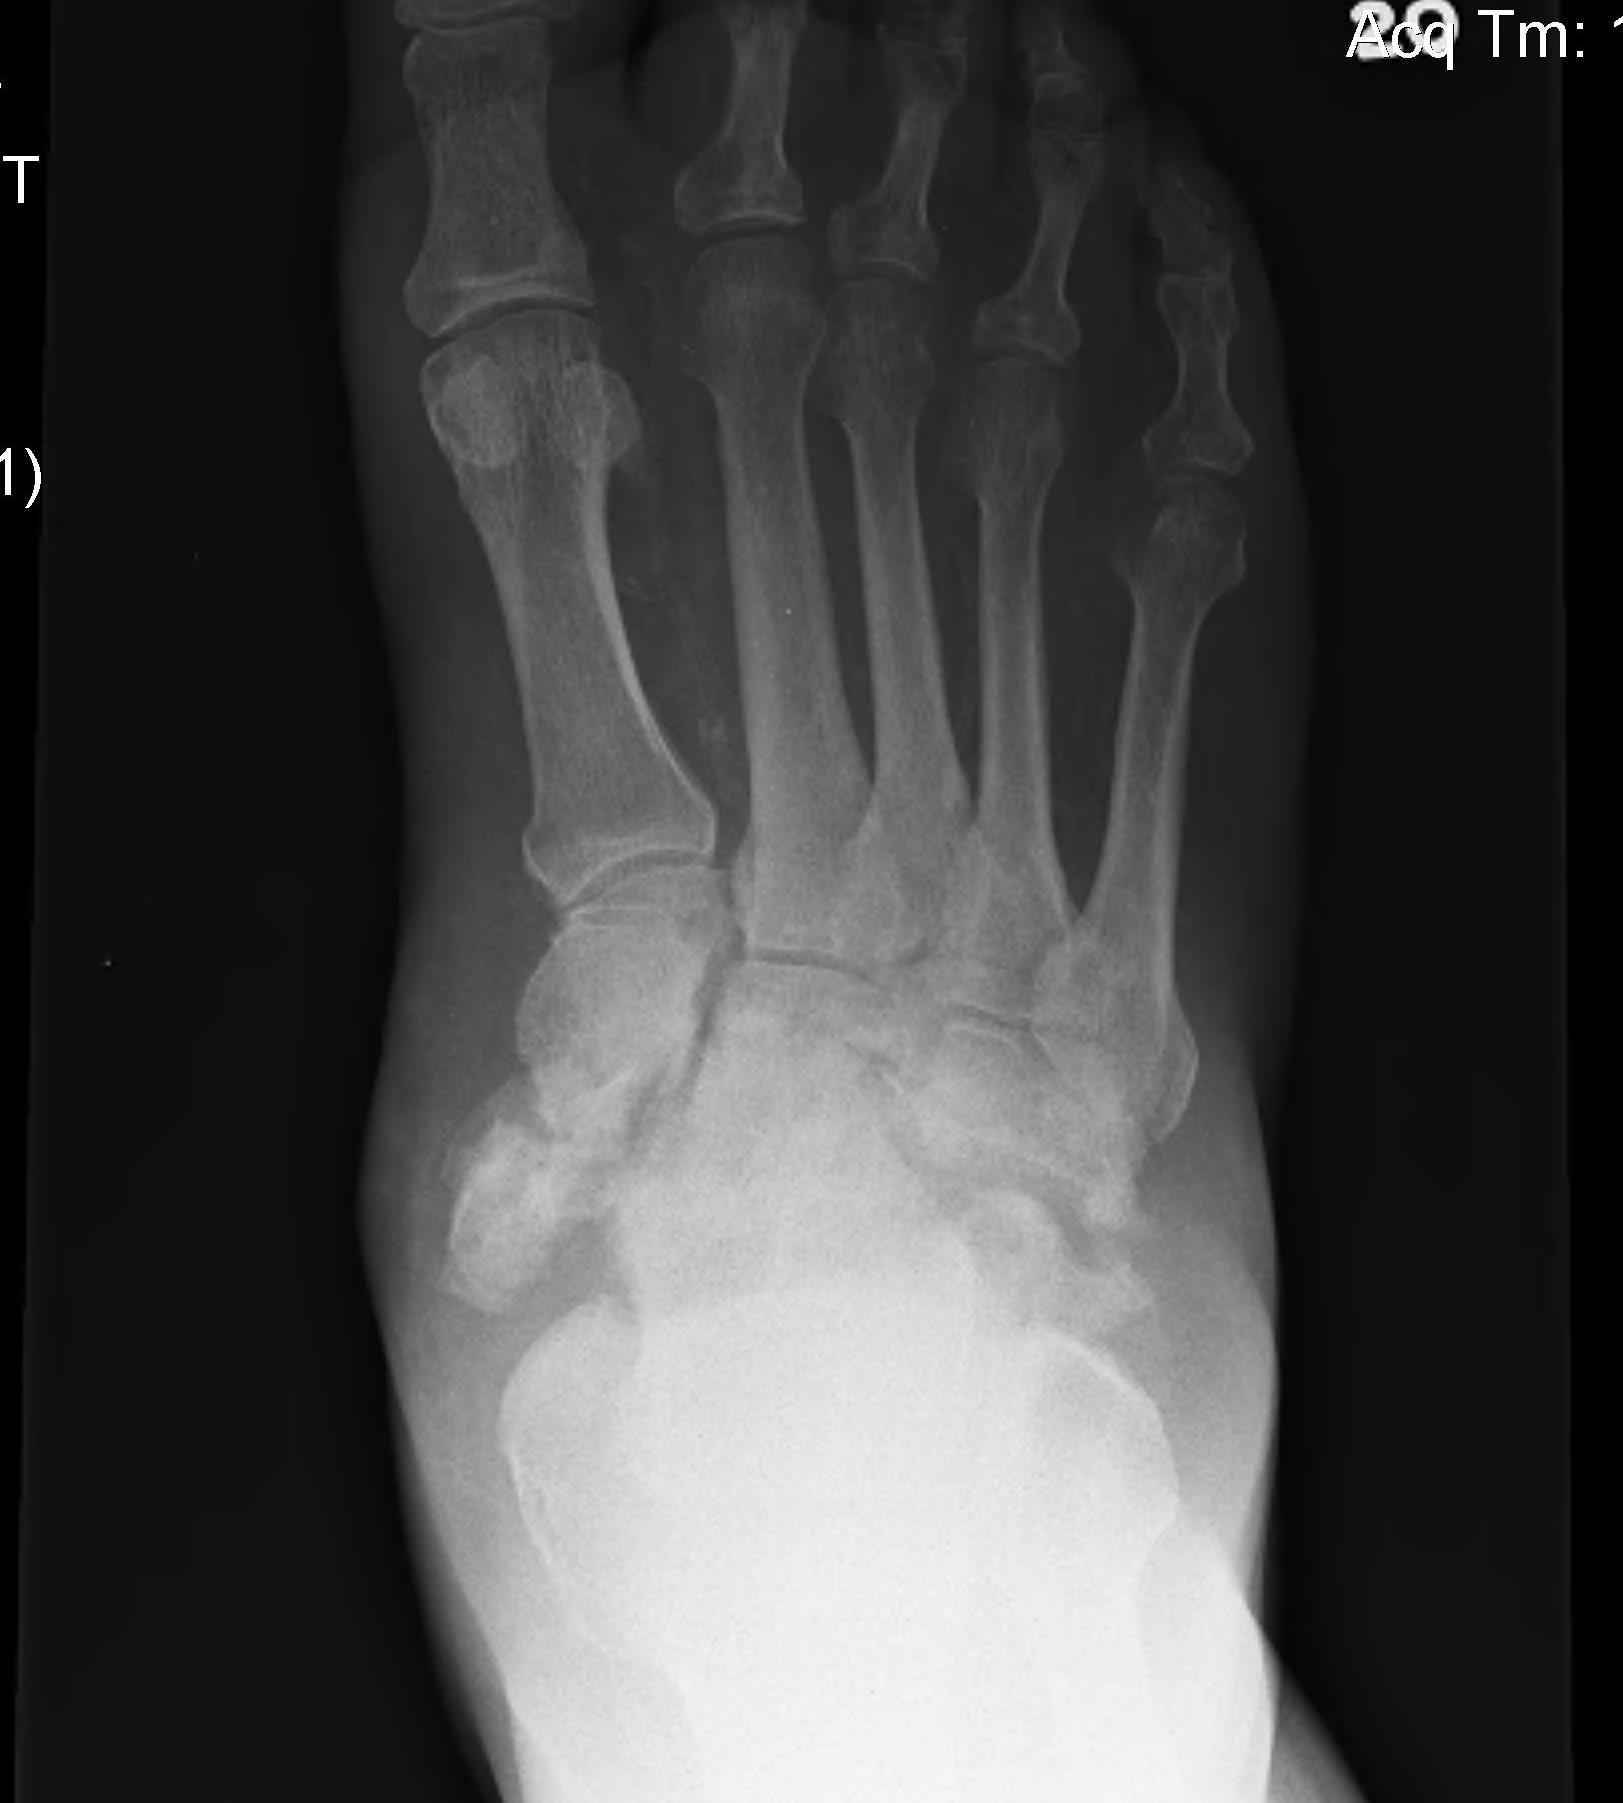

Kohler's Disease

Definition

Osteonecrosis of the navicular

Epidemiology

Present at age 4-6 years

M:F 5:1

Bilateral in 20%

Repetitive trauma to maturing ossific nucleus